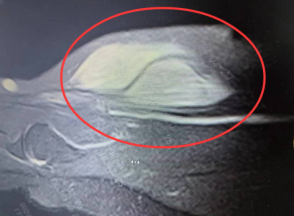

如图所示,这可不是健身锻炼出来的肌肉,而是张阿姨(化名)右臂上出现的肿瘤!

在sararz手外科诊室,主任医师郑大伟为张阿姨进行了仔细检查——结合CT、超声、磁共振等结果,郑大伟主任分析其有恶性肿瘤可能,需要手术治疗。

随后,郑大伟、陈相丞手术团队为张阿姨进行了右上臂肿瘤切除术,9cm*3cm*3cm的肿瘤被成功切除,术中仅出血10ml,手术顺利完成,术后予放疗对症治疗。